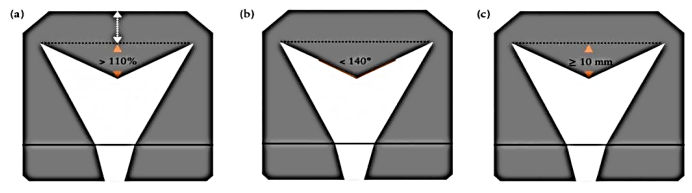

Observe a imagem a seguir.

Sobre as malformações uterinas, os critérios diagnósticos revelados na imagem se correlacionam a qual diagnóstico de malformação mülleriana?